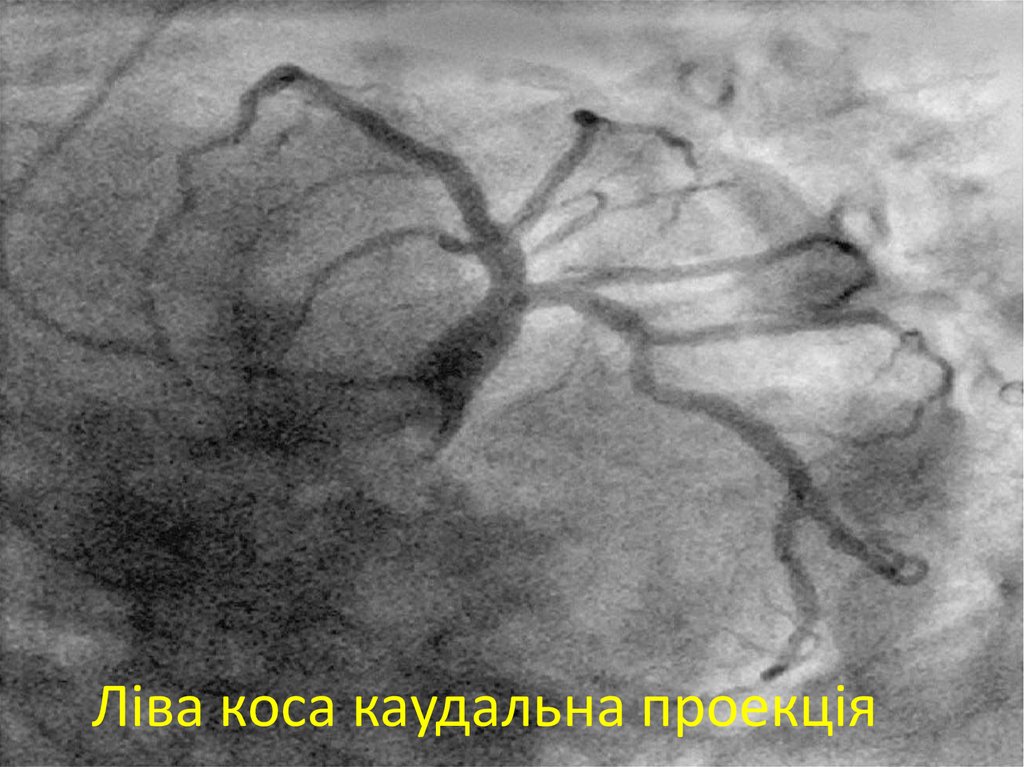

24. Ліва коса каудальна проекція

25. Ліва коса каудальна проекція

26. Положення ангіографа